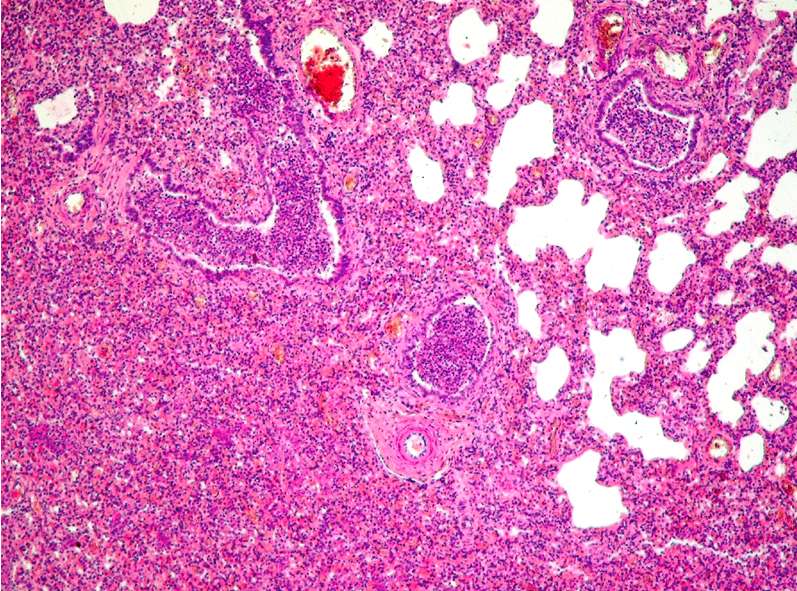

Identify:

Describe Macro appearence

and

this lesion is a complication of?

Bronchopneumonia

macro: multifocal changes. Inflammations are yellow.

-Usually complication of bronchitis